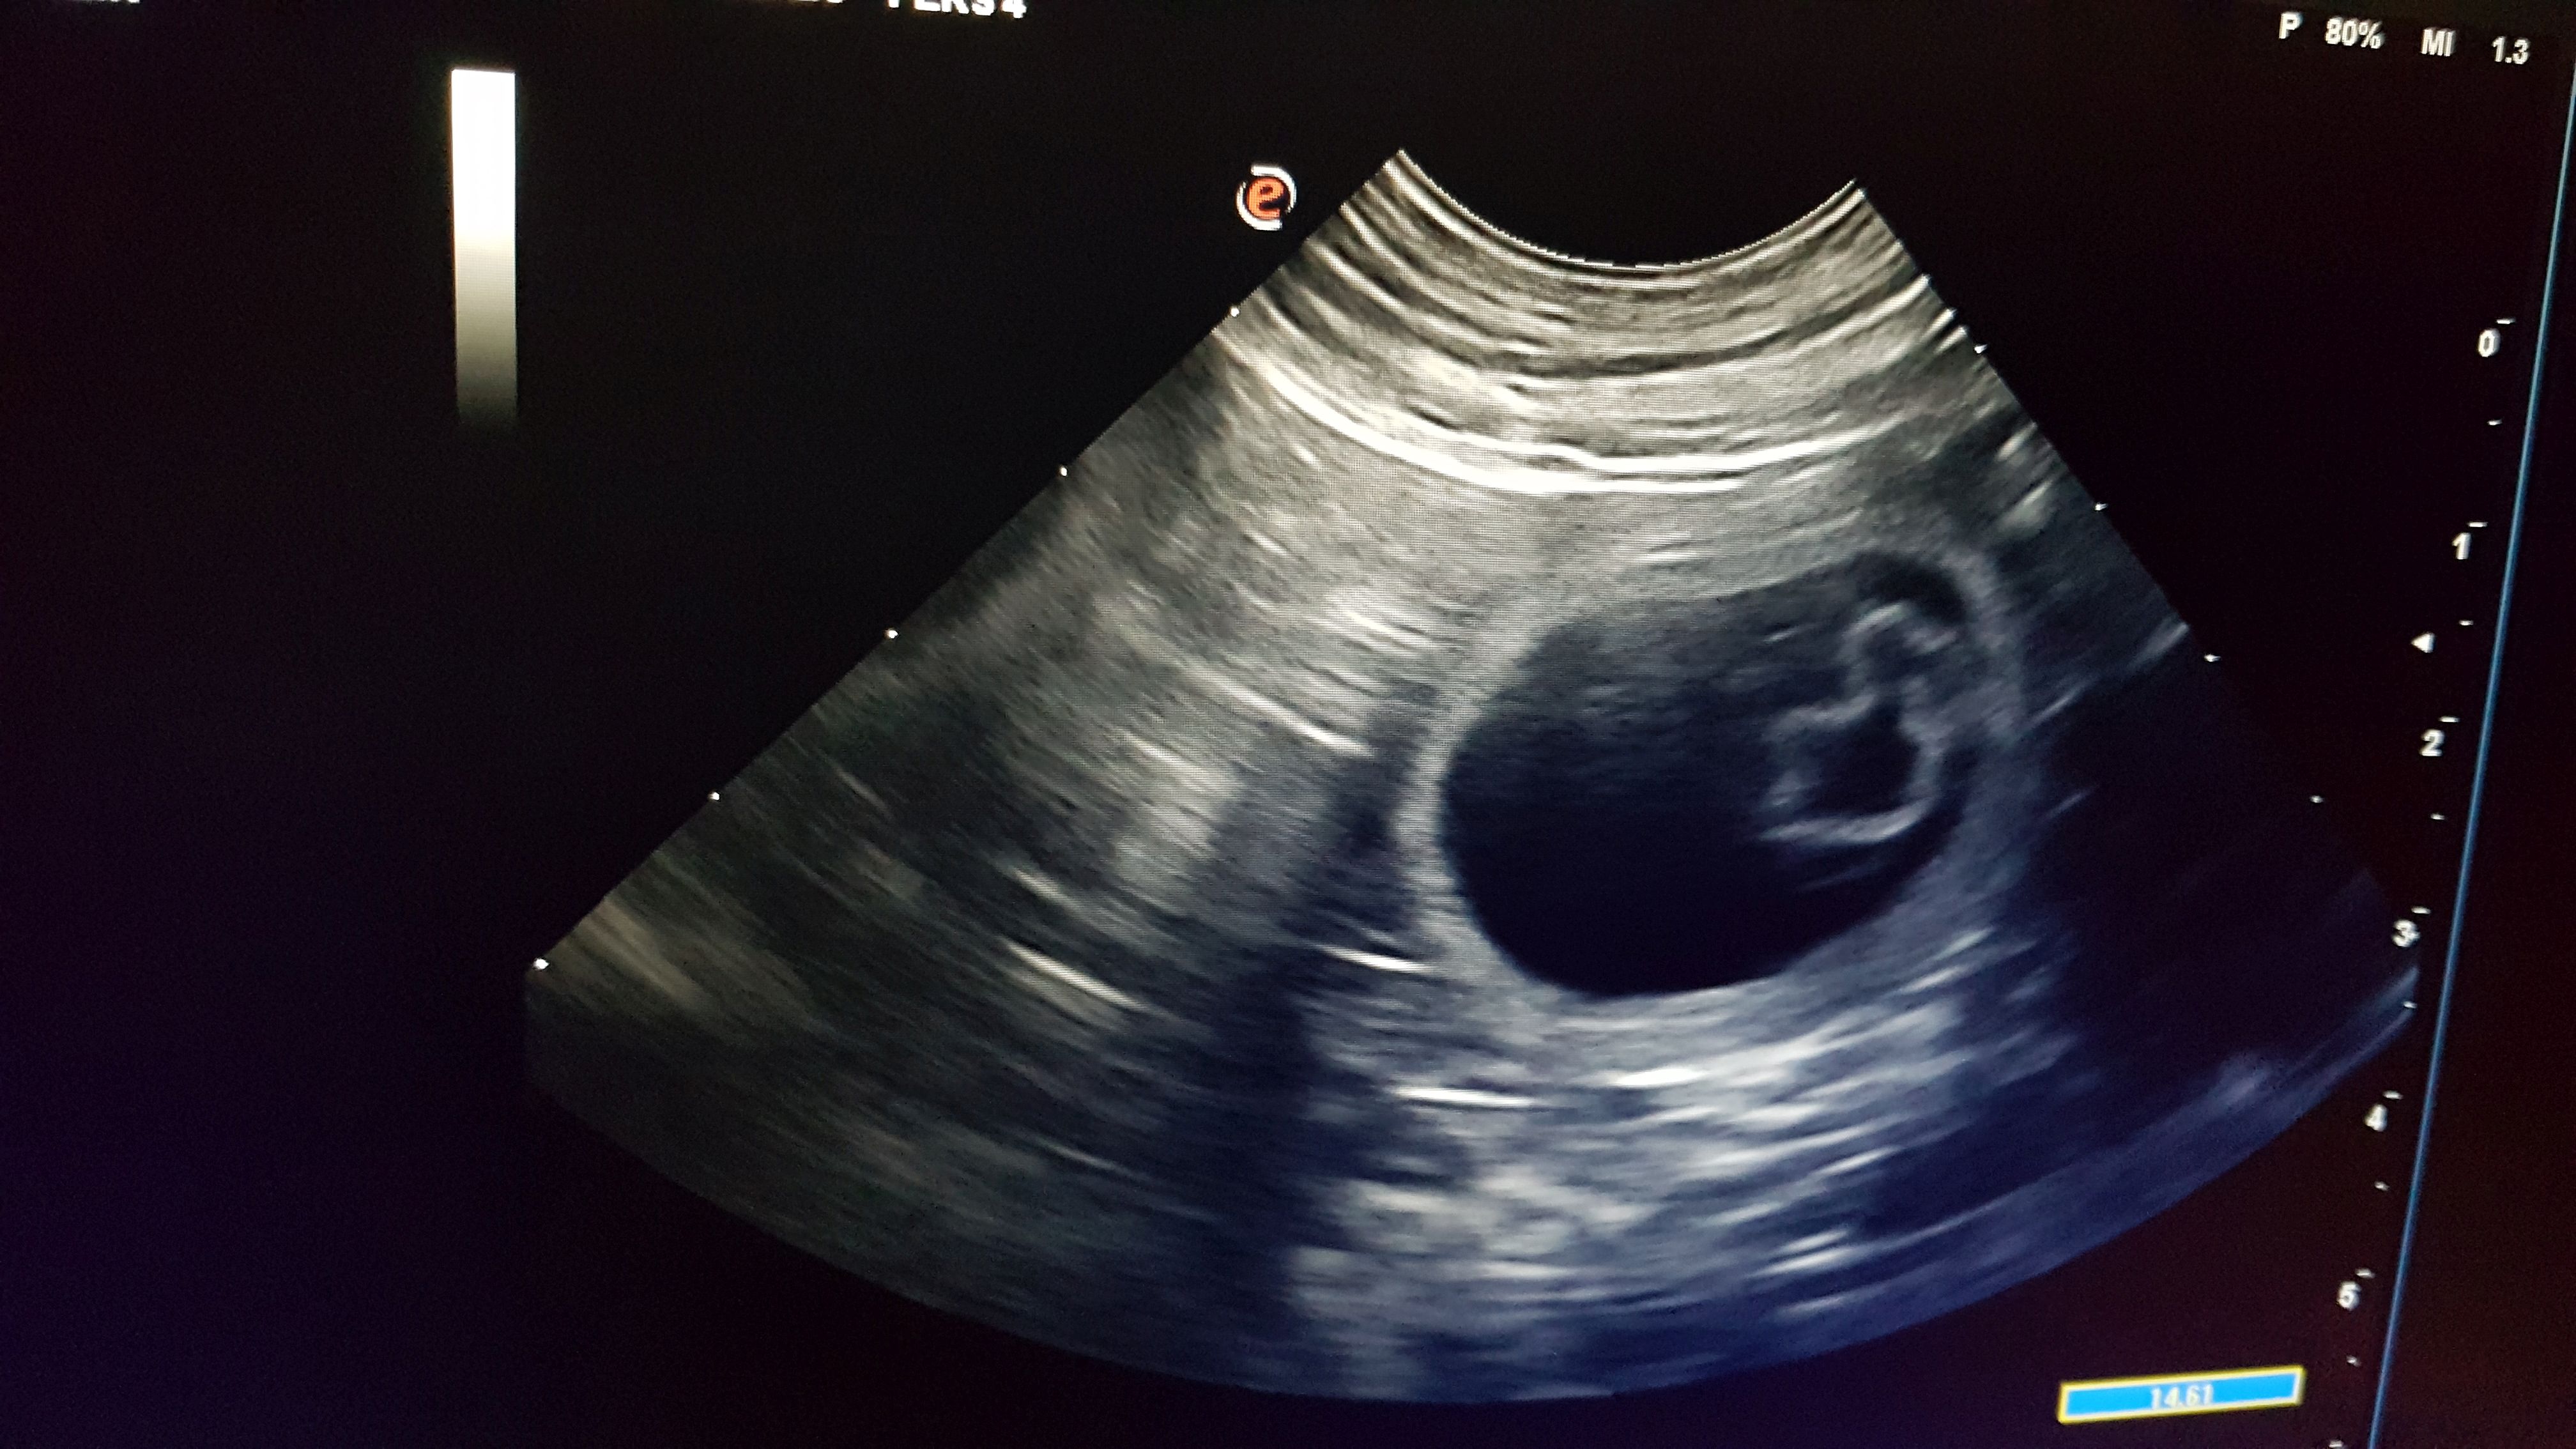

Heute ist DER Tag. Heute werden wir erfahren, ob Tia trächtig ist. Wir lassen sie mit Ultraschall untersuchen. Und da werden sie sichtbar: Hohlräume in schwarz mit kleinen Gebilden darin. Es hat geklappt!! Tia ist trächtig. Schätzungsweise sind es 6 bis 8 Fruchtanlagen.